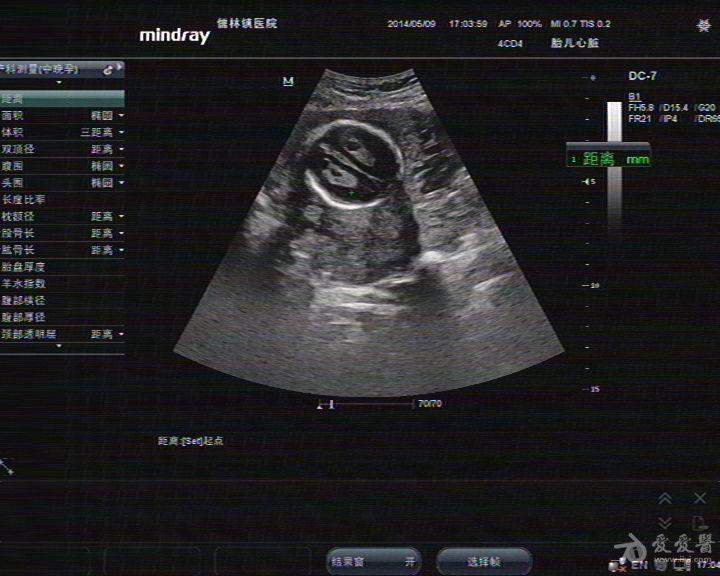

胎儿颅内结构超声切面

胎儿颅内结构超声切面,胎儿脑部超声切面图解

胎儿超声标准切面详解

看看这个胎儿颅内情况,见过没有,考虑什么啊 - 超声版

【新手必看】中孕期胎儿超声检查 — 颅脑和颜面部分

胎儿脑部液暗,大家觉得是什么 - 超声医学讨论版 - 医

胎儿脑部超声切面图解